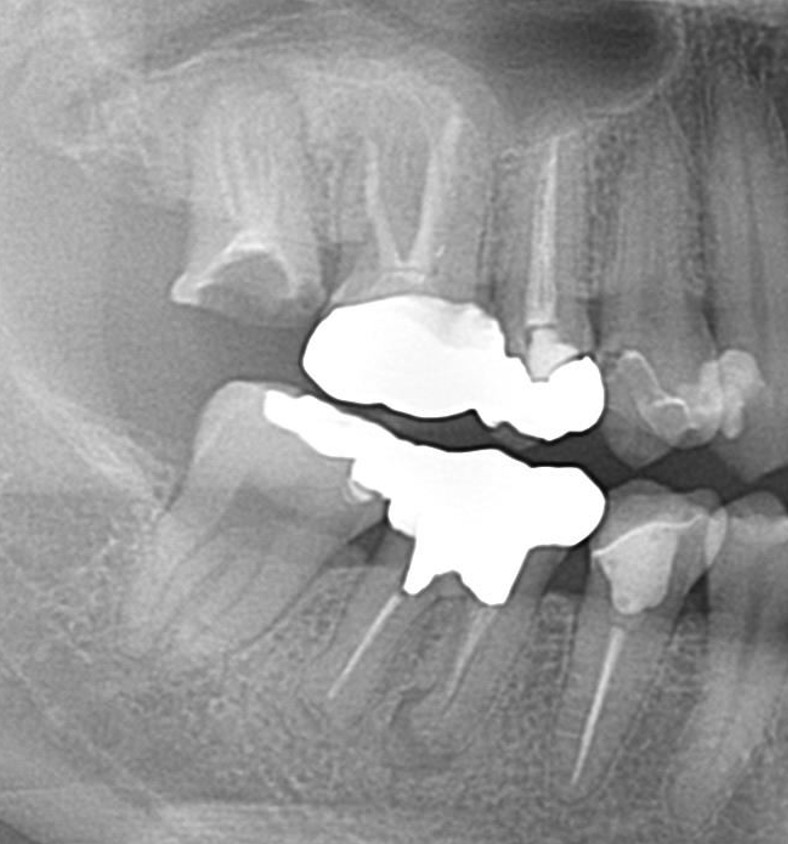

症例7

| 項目 | 詳細 |

|---|---|

| 患者様データ | 50代 男性 |

| 来院時の主訴 | 「右上の歯が噛むと少し痛い。」 |

| 医院の診断 |

虫歯の再発、未処置根管の存在 |

| 通院期間 | 4か月 |

| 来院回数 | 5回 |

| 治療費 | 220,000円(税抜) 《内訳》 精密感染根管治療80,000円、ファイバーポストコア20,000円、セラミック治療120,000円 |

| リスクと副作用 | ①根管治療歯は長期的には破折するリスク ②メインテナンスが必要 |

| ココがこだわりのポイント☝ |

上顎の小臼歯は1根か2根が通常ですが、この歯の場合なんと3根!それも途中で分岐しており4根管ありました。 これはかなりの確率で1%未満と思われます・・・術前のCT検査で発見されました。 そんな歯をラバーダム防湿とマイクロスコープを使用して丁寧に治療を行いました。 再根管治療のため、殺菌性があり歯を補強することのできる根管充填材料を使用しています。 |